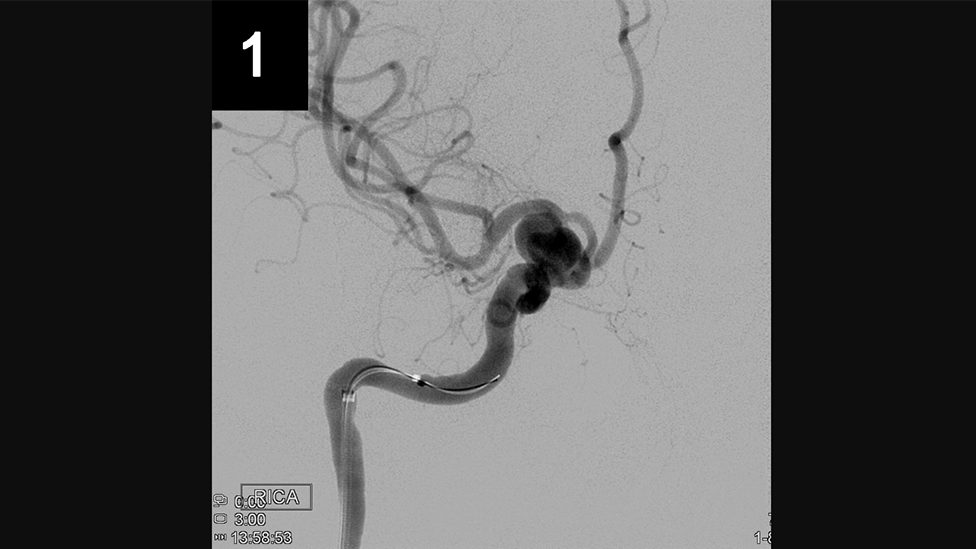

Primary Coil Embolization, Technique: Aneurysm

Primary Coil Embolization: Treats aneurysm from the inside rather than the outside. Fill aneurysm with embolic coils in order to obliterate blood flow.